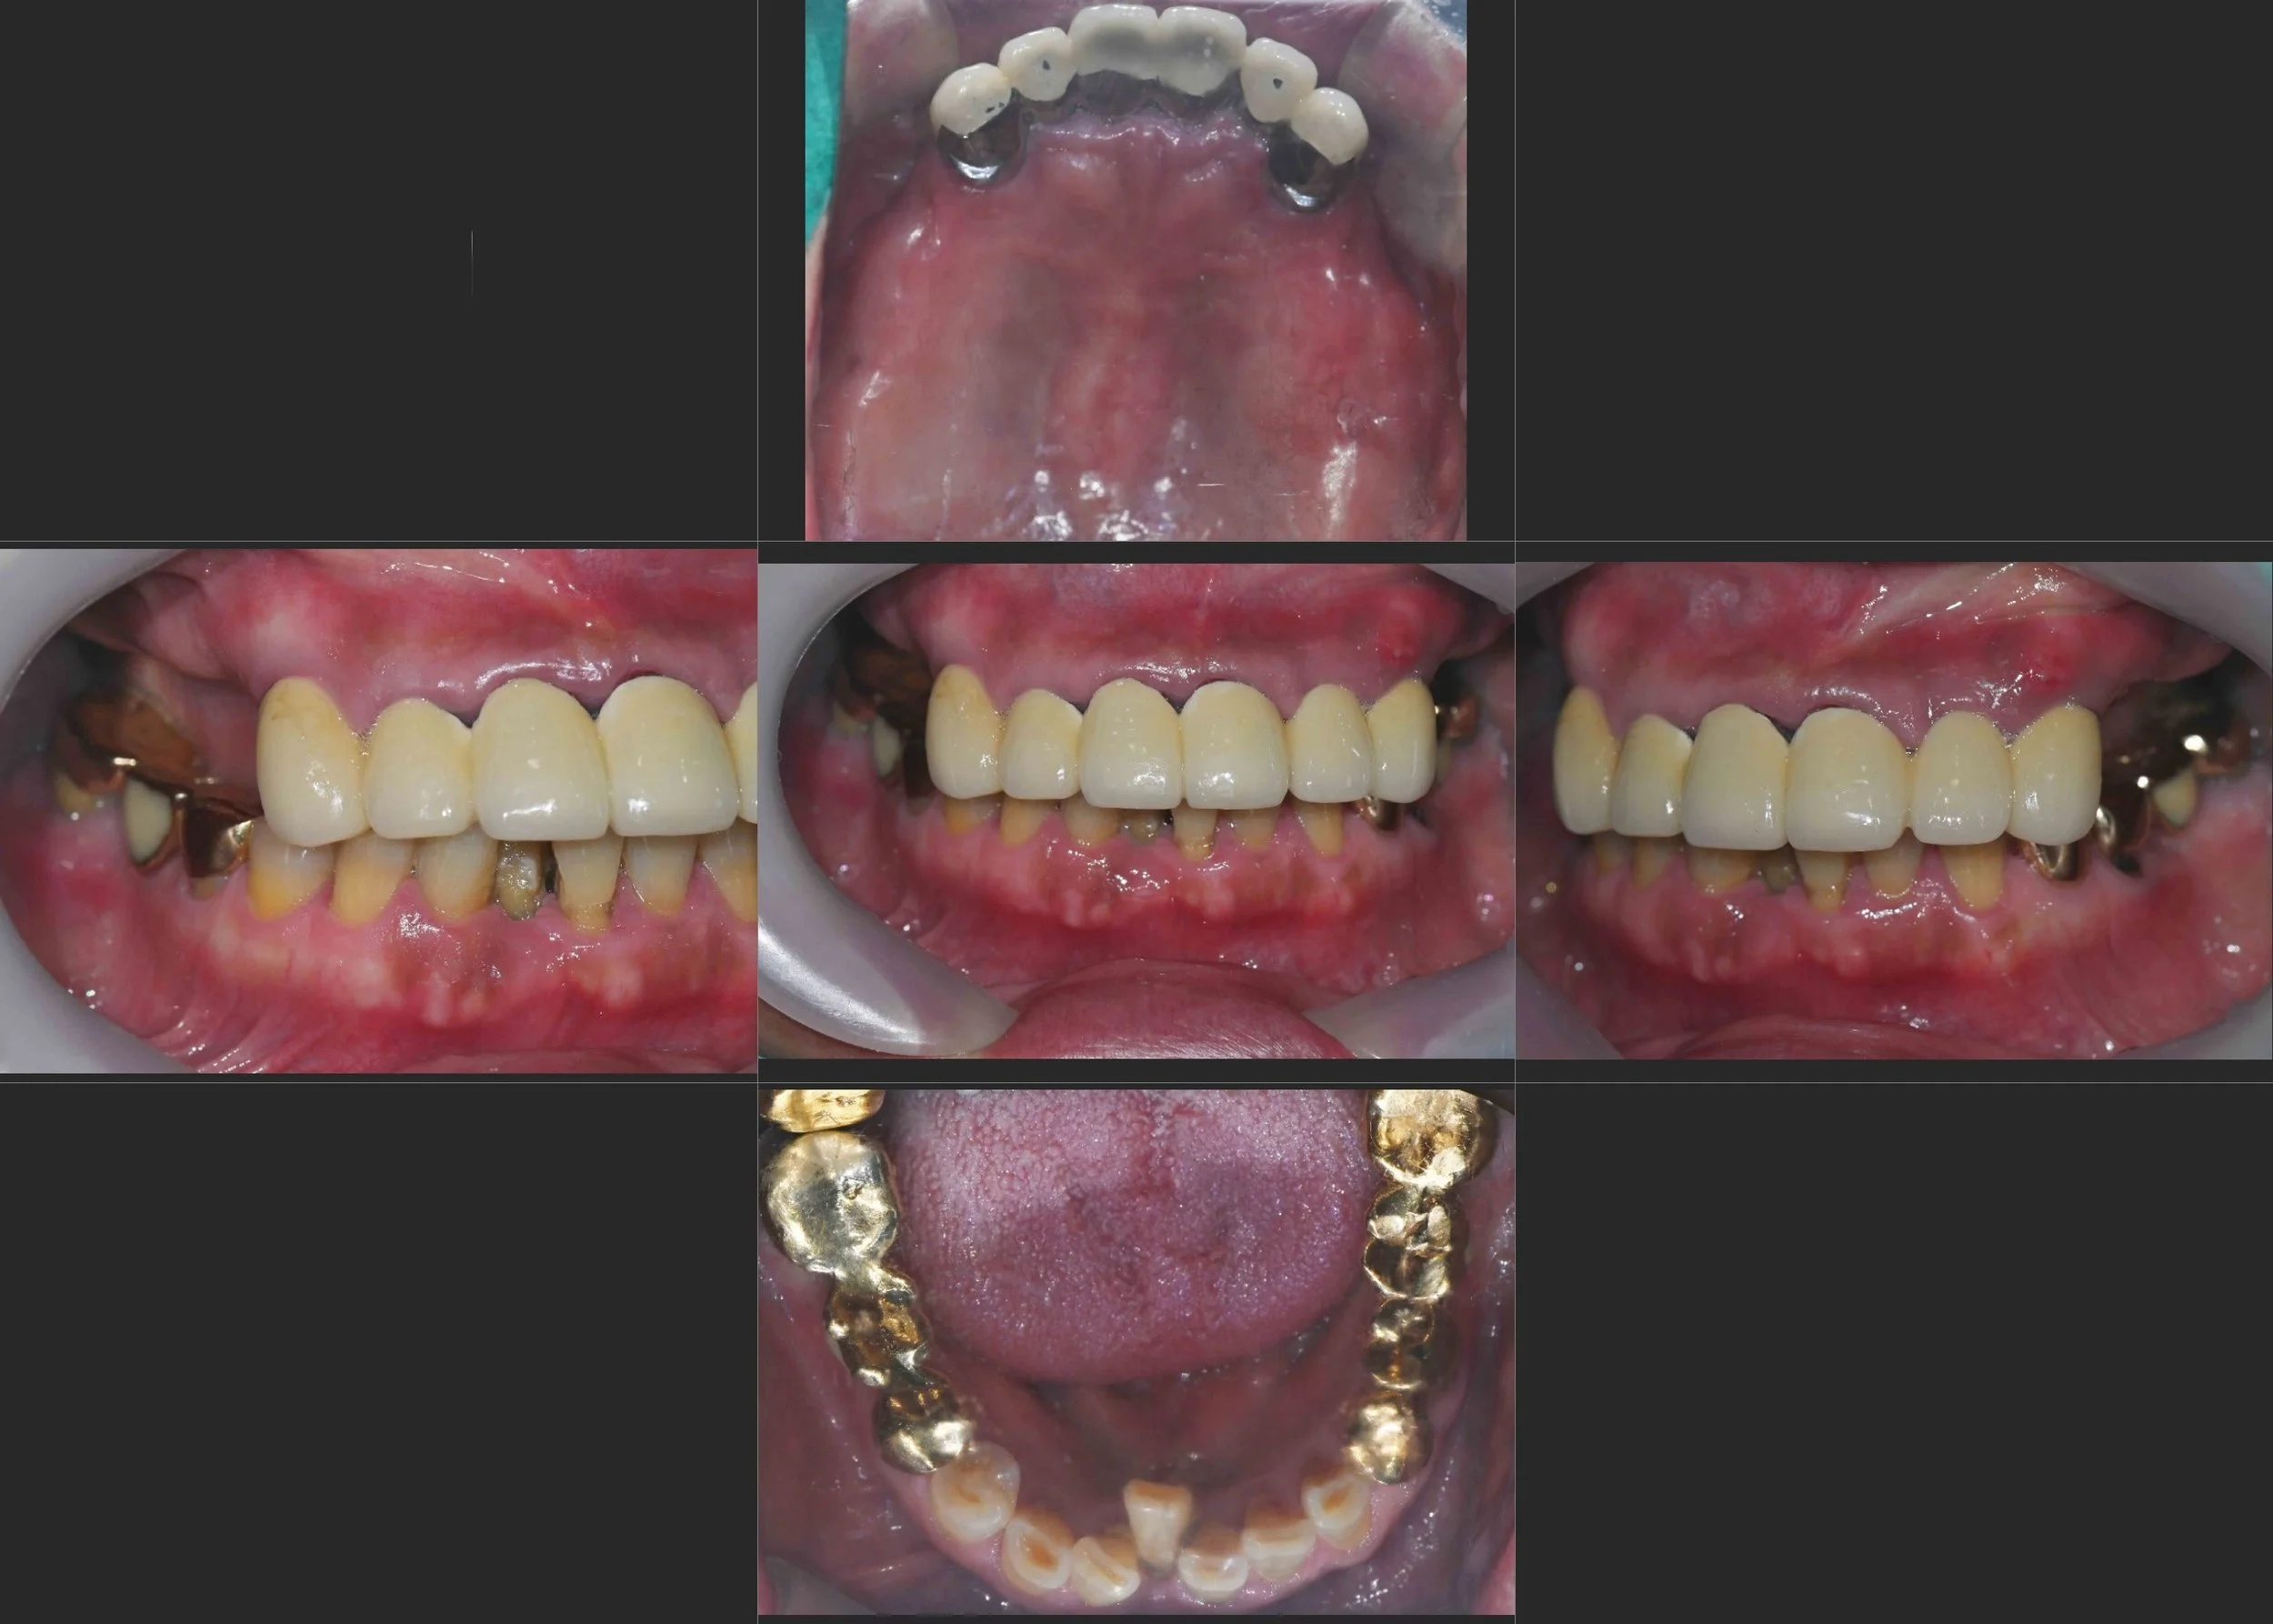

INTRA ORAL - BEFORE

INTRA ORAL - AFTER

• Failing Anterior Bridge: The existing maxillary anterior bridge exhibited significant mobility due to the poor condition of the abutment teeth.

• Severe Mandibular Crowding: Due to long-term posterior tooth loss and lack of space, the mandibular anterior teeth showed significant lingual displacement (lingual position).

• Occlusal Collapse: The loss of posterior support led to a collapse in the vertical dimension, making functional chewing impossible.